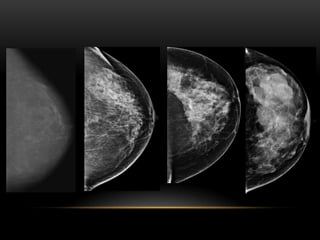

PATRÓN DE TEJIDO

PATRÓN DEL TEJIDO GLANDULAR

1. Fibroadiposo escasa cantidad(- 25 %

glándula)

3. Densidad heterogénea (51-75% glándula)

4. Extremadamente denso(+ 75% glándula)

FIBROGLANDULAR ESCASA CANTIDAD

FIBROGLANDULAR MODERADA CANTIDAD

HETEROGENEAMENTE DENSO

EXTREMADAMENTE DENSO